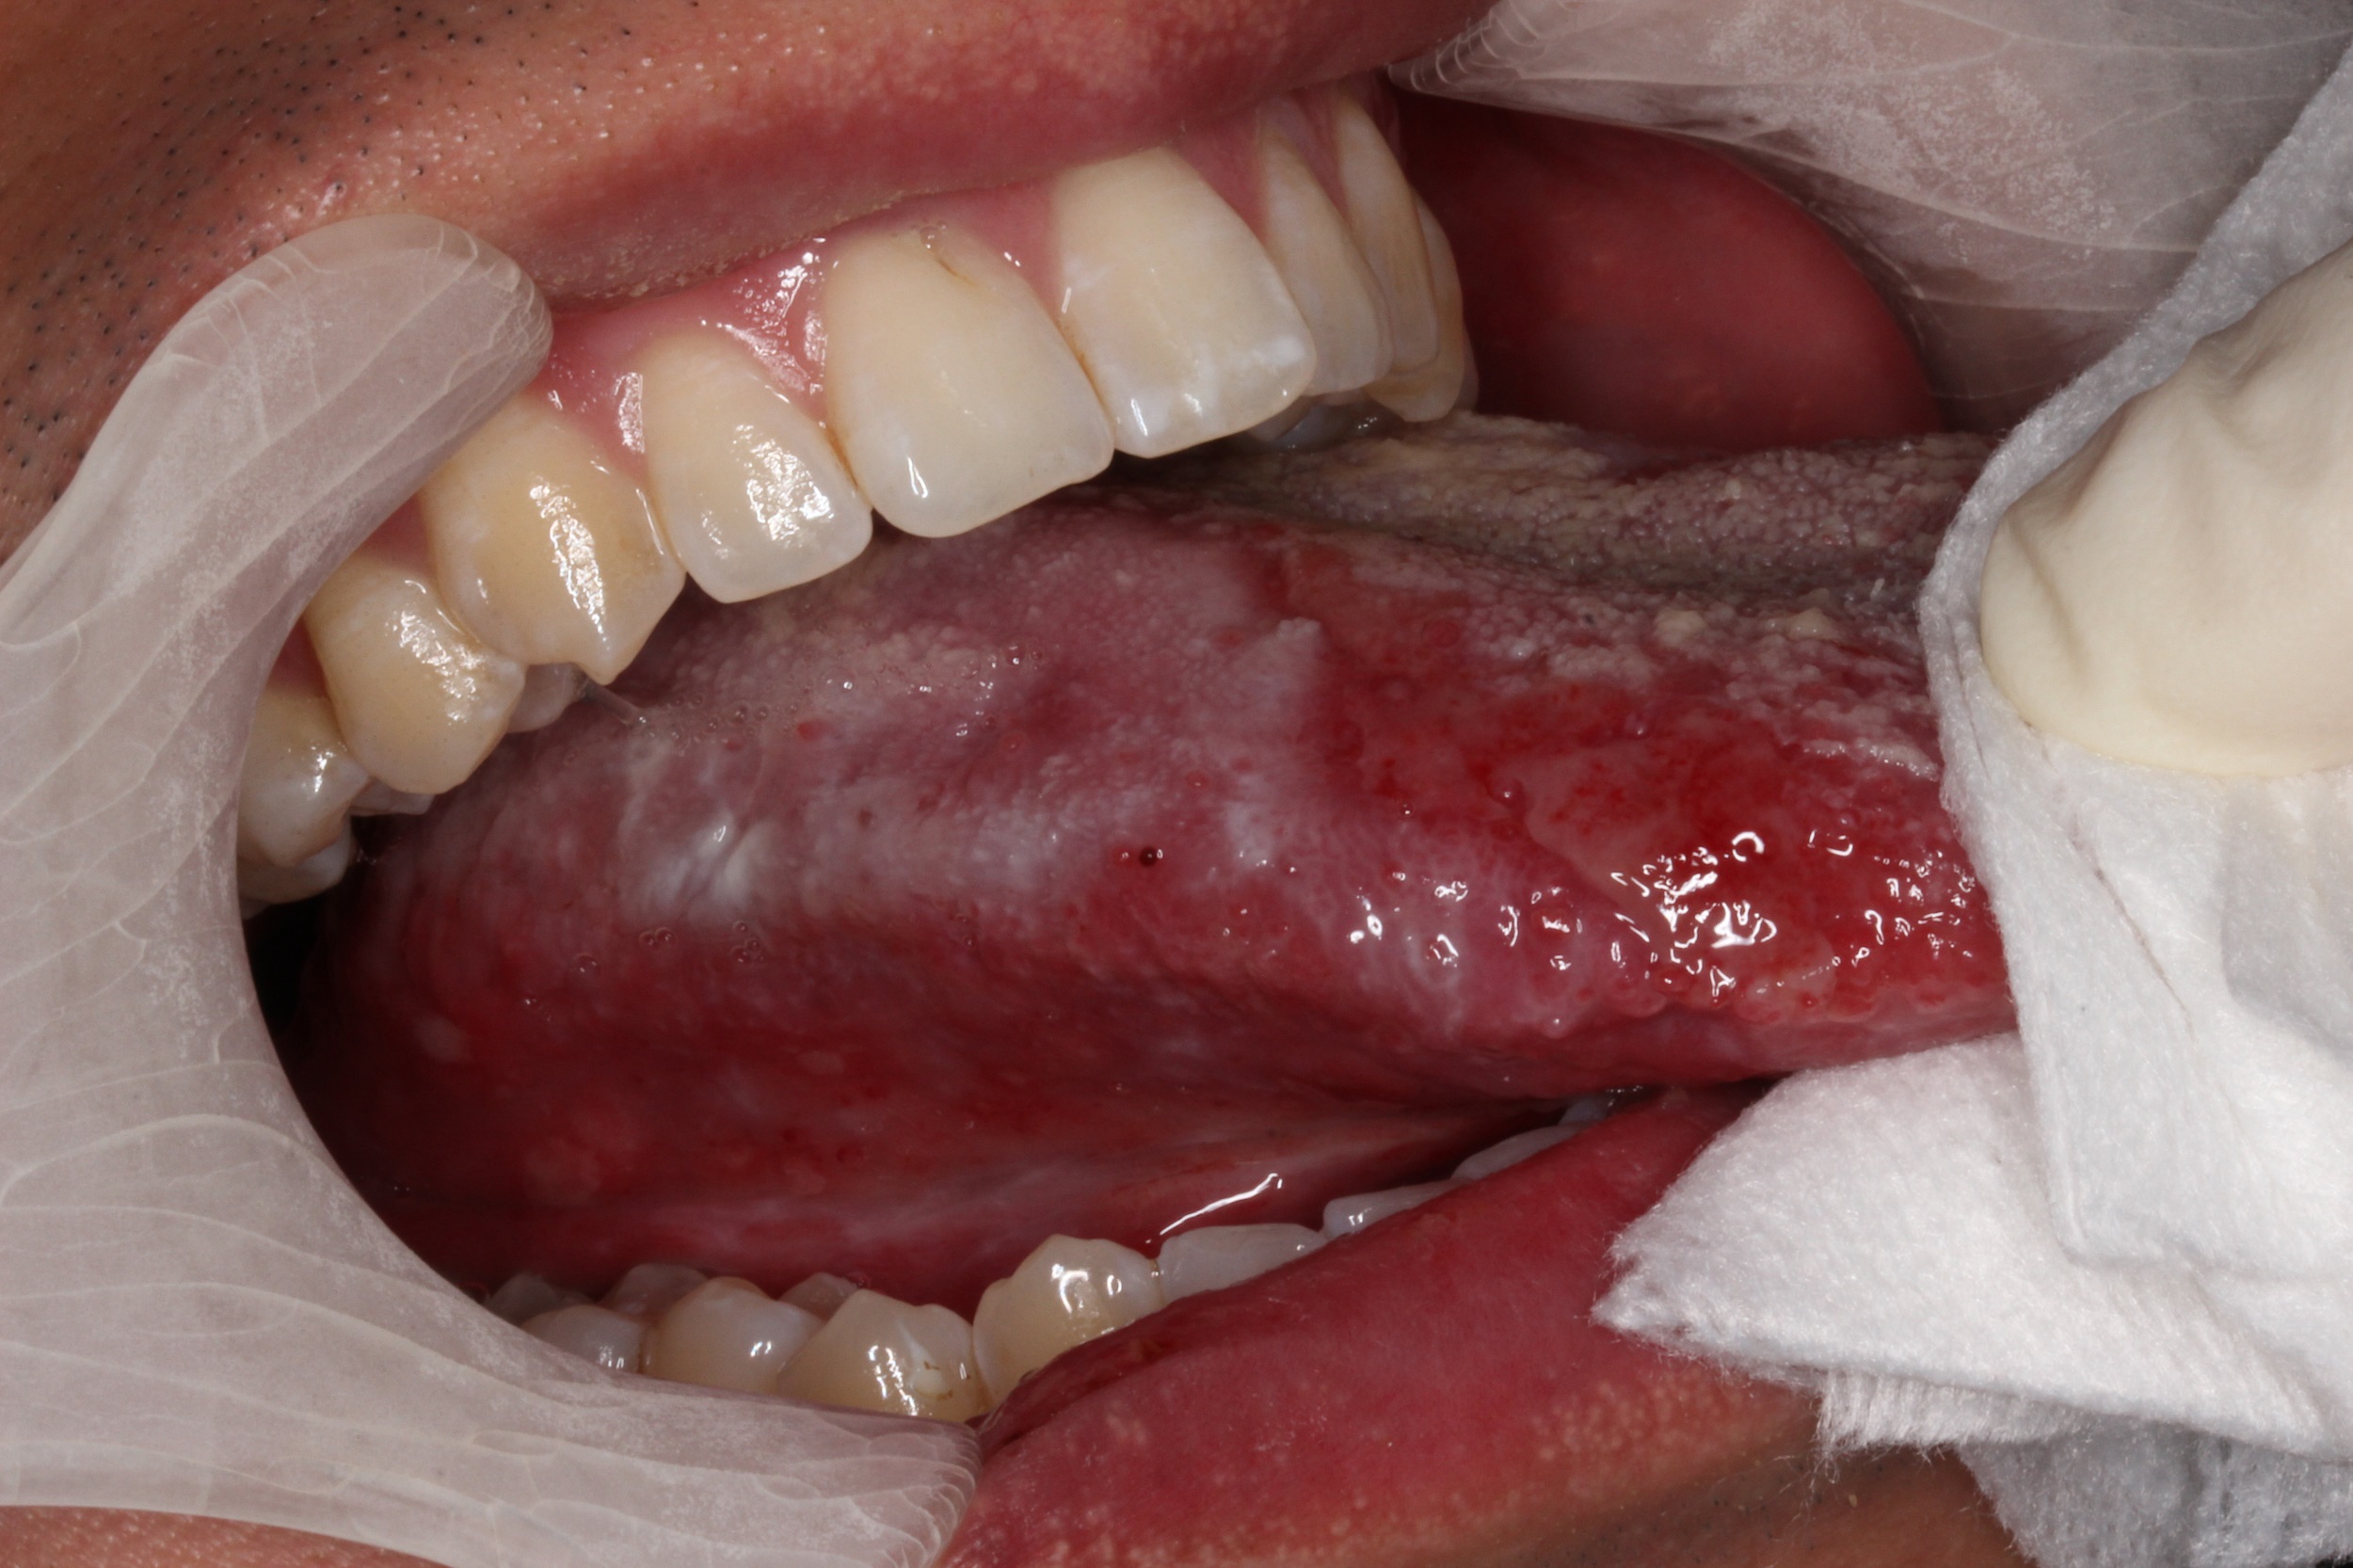

精彩病例口腔扁平苔藓患者的舌部白斑

【病例讨论】这是扁平苔藓吗? [病例帖]